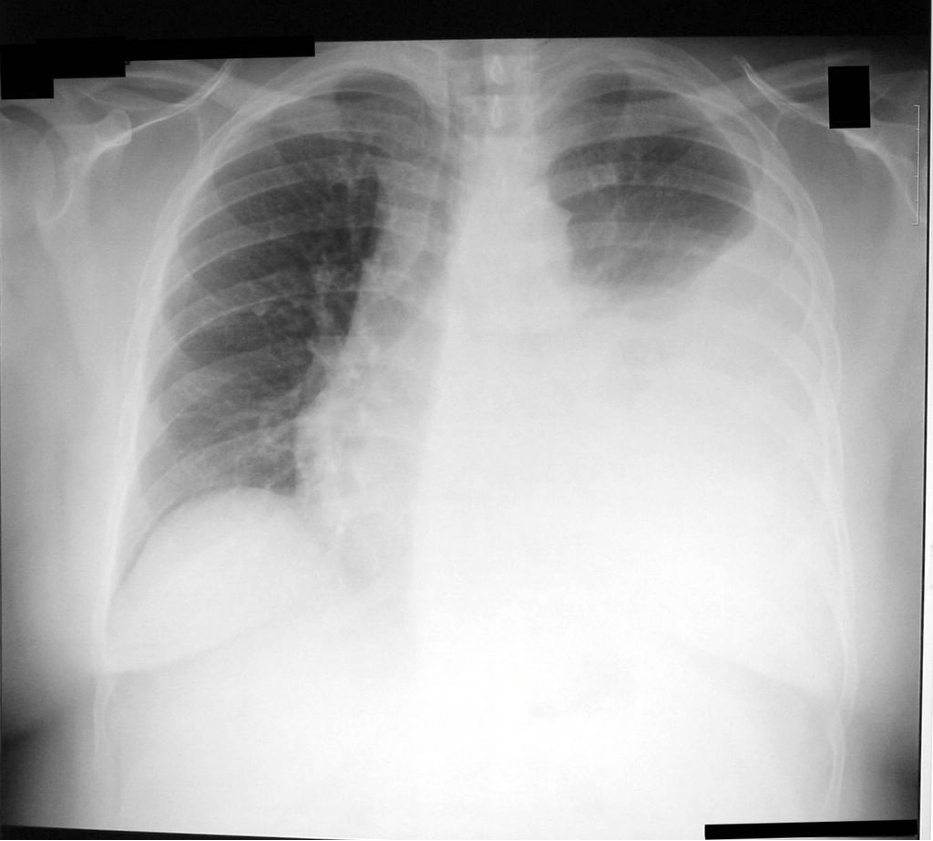

Q

what does this CXR show?

A

left-sided pleural effusion

- blunting of costophrenic angles

- blunting of cardiophrenic angle

- fluid in fissures

- fluid level

- mediastinal shift away from effusion in larger volumes